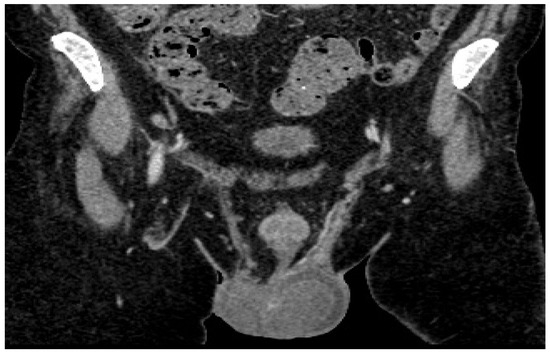

A spermogram was performed which revealed the following: color, yellowish-white, slightly opalescent; viscosity, normal (at 2 h); quantity, 3.0 mL (VR: 2–6 mL); pH, 8.0 (VR: 7.2–8.0); sperm count/mL, 0.0 mil sperm cells/mL (VR: 20–200 sperm cells/mL); round cells, 5.5 mil/mL; cellularity consisting of mononuclear with morphology suggestive of blastic (lymphoblastic) cells, macrophages, polymorphonuclear neutrophils, and very rare germ cells; microbial flora was present. Flow cytometry was recommended for the accurate identification of blast-like mononuclear cells (Figure 3a–c).

Consequently, as an alternative to orchiectomy to establish the diagnosis of certainty, the immunophenotyping of spermatic fluid (Figure 3a–c) was performed; the method, according to our research and knowledge, has never been performed in Romania and, therefore, there is no standardized protocol.

The immunophenotyping of the spermatic fluid (PANEL CD45, CD3s, CD3ic, CD4, CD5, CD8, and CD99) identified 36% atypical cells with the following immunophenotype: CD3ic+, CD3s−/+, CD99+, CD4−, and CD8−. The pathological product is infiltrated with atypical cells with an immunophenotype concordant with that of the underlying disease (ALL T)—analyses were performed using a Dx FLEX analyzer with 3 lasers and 13 colors (5 colors were used).

Figure 3. Spermogram. (a) Simple stretch smear technique—blasts with nucleoli; (b) mononuclear with morphology suggestive of blastic cells; (c) cytospin—concentration technique, mononuclear; microbial flora present.